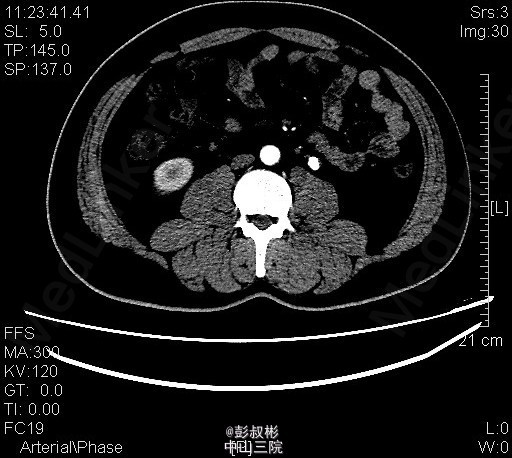

1、体检发现左输尿管结石2月 2、患者2月前体检发现左输尿管结石,无腰痛,无其他部位反射痛,无发热,无恶心,当时未给予治疗。今为求进一步治疗来我科住院,起病以来患者一般情况尚可,体重无下降。

3、查体:双肾区无红肿、隆起,左肾区叩击痛(-),右肾区叩击痛(-),左侧肋脊点、肋腰点压痛(-),右侧肋脊点、肋腰点压痛(-)。腹平软,左侧输尿管走行区压痛(-),右侧输尿管走行区压痛(-),膀胱区无膨隆,压痛阴性 4、辅助检查: 我院 腹部平片 左输尿管上段结石 ;泌尿系b超 前列腺增大;右肾多发结石;左肾形态失常;左输尿管上段结石并左肾积液。CT示左输尿管上段结石、左肾小结石

5、诊断:左输尿管上段结石并左肾积液 6、入院后予以完善术前检查,未见明显手术禁忌,在全麻下行“单孔腹腔镜下左输尿管切开取石术”,术后予以一级护理,心电监护,低流量吸氧,营养支持,抗炎对症治疗。术后注意观察事项:保持引流管及尿管通畅,留意尿量及引流量